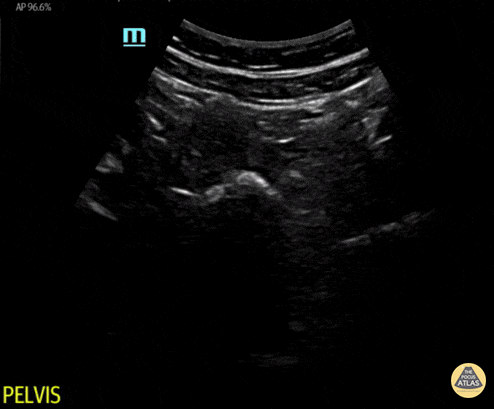

Peds-Trauma

abnormalluq, abnormalruq, msk, traumanormal